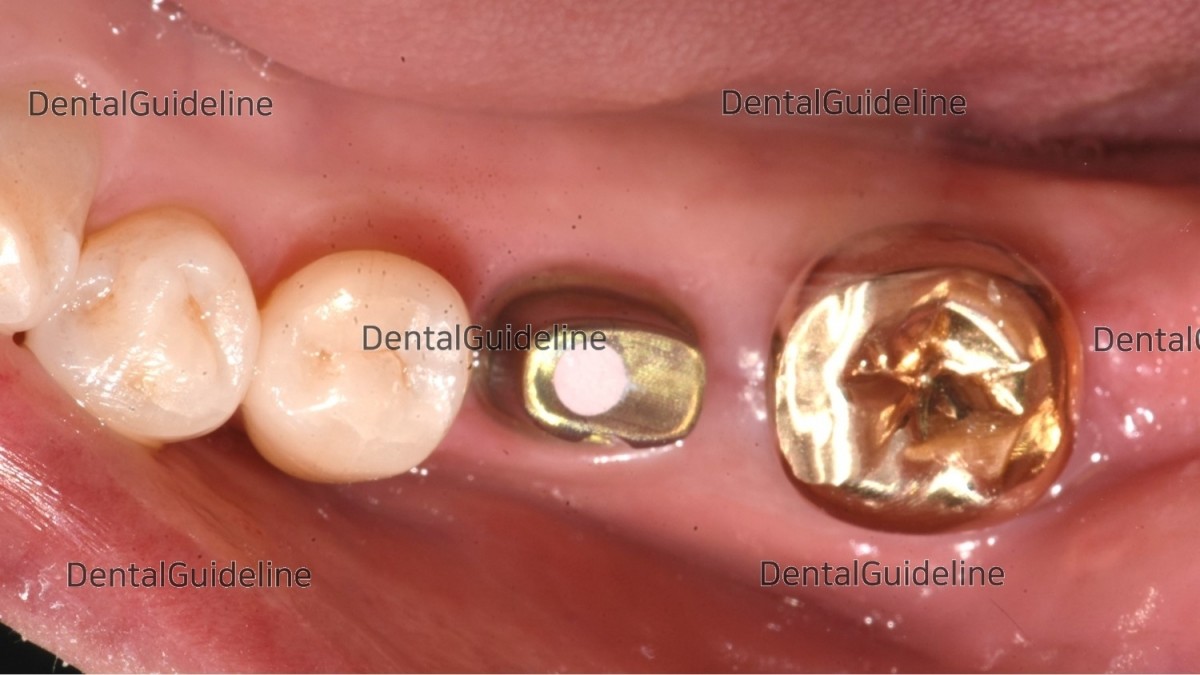

10weeks post-op. intraoral photo on the day of ISQ measurement and impression taking.

Intra-oral photo on the day of restoration.

The abutment was connected to the fixture.

The screw hole was filled with temporary filling material for retrievability.